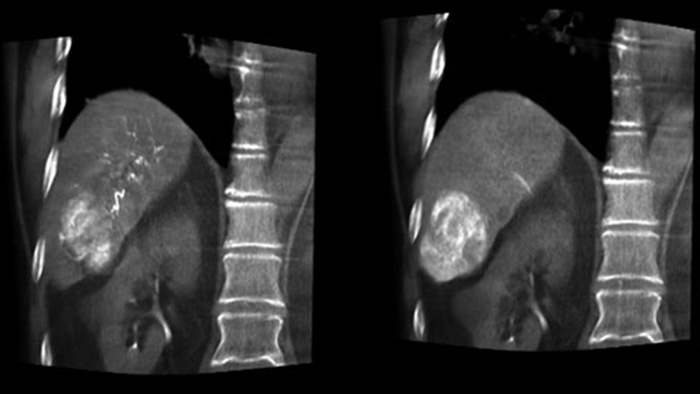

Una adquisición 3D posterior a la embolización le permite ver el depósito dirigido del material embólico, como Liopidol o perlas radiopacas, en el tumor.5.

Dual View permite ver de forma simultánea la imagen 3D de la fase arterial antes de la embolización y la imagen después de la embolización para evaluar el fin del tratamiento.